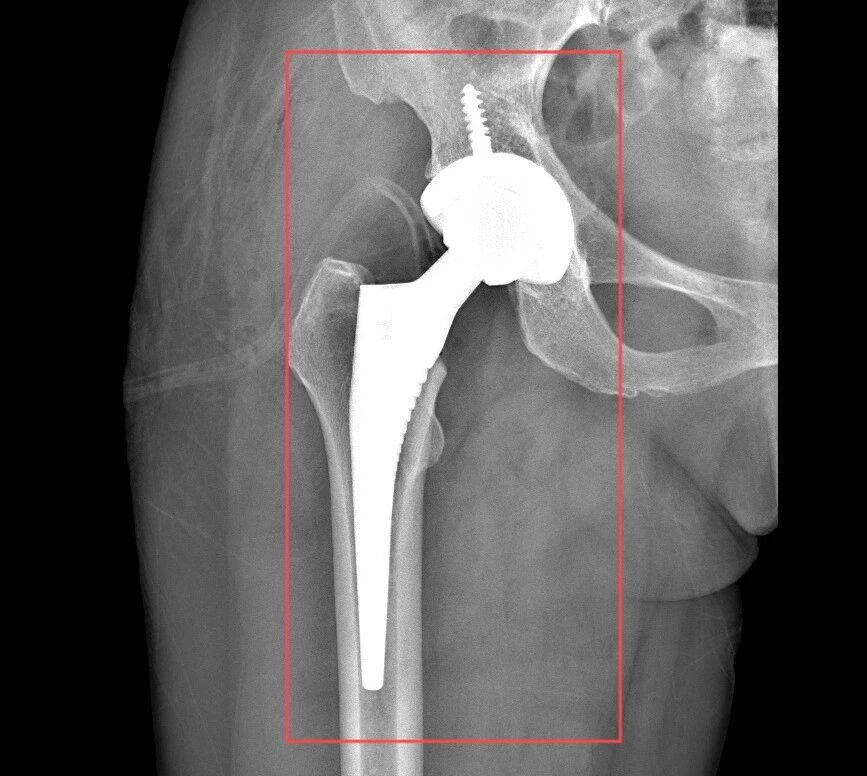

患者术前、术后CT

随后,张锡光带领MDT联合会诊团队再次针对患者病情及诊疗方案进行认真研究,反复分析讨论,确定由张锡光主刀,创伤中心副主任蔡志荣协助,为患者实施全髋关节置换手术;其他相关科室则为患者可能出现的突发情况做好相应准备。

无影灯下,张锡光以精确至毫厘的动作实施着手术操作。医疗团队在默契协作中形成精密的工作闭环,每个环节都如齿轮啮合般严丝合缝。基于患者特殊的身体状况,张锡光精准把握手术节奏,凭借行云流水般的手术技法,仅用半小时便完成创口仅8cm大小的微创手术,全程零输血的操作既保障了患者机体代偿能力,更赢得关键性康复窗口期。术后次日清晨,杨女士已能借助助行器完成自主移行训练。康复医学科团队更创新性构建起三管齐下的复健方案,涵盖运动功能重塑、营养代谢优化及心理韧性建设等多维度的精准干预,用医学专业与温暖人文编织起全周期的康复守护网。

患者术后第二天在助行器辅助下行走